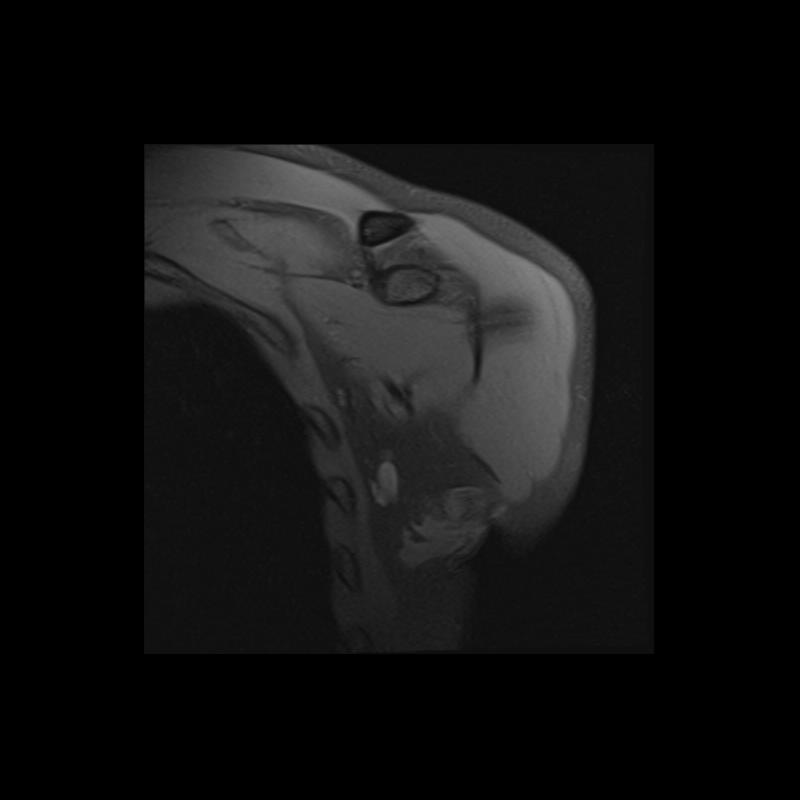

Shoulder MRI Anatomy